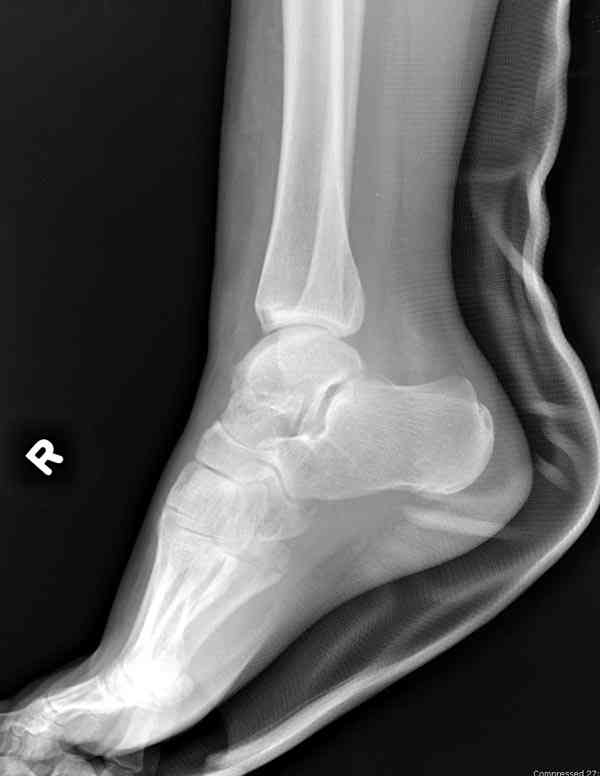

Случай с множественным оскольчатым переломом тарана оперированный из двойного доступа.

Через 2 мес.:

Через 8 мес.:

Через 14 мес.:

Для оценки состояния нужны дополнительные исследования, например

повторили рентгенограммы и доделали проекции, к единому мнению все еще не пришли

На ренгенограмме не уловил многоскольчатость тарана, чтобы доказать, конечно, можно было исследовать на КТ, потом КТ дает ориентацию фрагментов.

Два фрагмента суставной поверхности тарана можно восстановить боковой компрессией шурупами и дополнительно костная пластика.

Решили не связываться с остеосинтезом, а сделать сразу берцово-пяточный блок. Снимки в приложении.

По завершении удлинения, наверно, заштифтуем.

Комментарии/критика приветствуются.